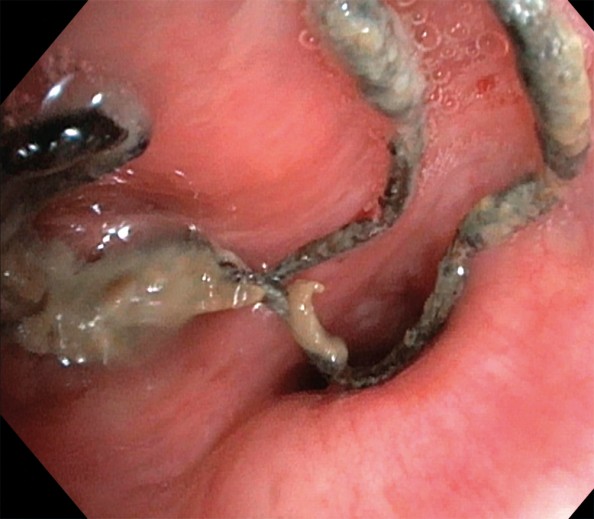

På bildet, tatt ved bronkoskopi, ses suturmateriale og purulent slim som ligger endobronkialt, nær ostiet for det apikale underlappssegment på høyre side.

Pasienten er en kvinne i 50-årene. Som barn ble hun operert med partiell høyresidig underlappsektomi. Man lot det apikale underlappssegmentet stå igjen, og det ble brukt ikke-resorberbar tråd. Etter operasjonen har hun hatt tilbakevendende nedre luftveisinfeksjoner, alt fra bronkitt til pneumoni. Forut for den aktuelle bronkoskopien ble det gjort CT thorax som avdekket abscessutvikling (CT-bilde). Ved utredning fant man ingen underliggende immunsvikt eller andre forklaringer på infeksjonstendensen. Hun røyker daglig, men har ingen obstruktiv lungesykdom. Suturmaterialet som ble avdekket ved bronkoskopi var i retrospekt synlig på CT thorax-bildet, men kunne muligens mistolkes som sekret i luftveiene.

Suturmateriale er som et fremmedlegeme og fremmer dannelse av en biofilm og bakteriekolonisering. Dette er høyst sannsynlig årsaken til gjentatte pneumonier og utviklingen av lungeabscess (1) . De synlige suturene lot seg fjerne med tang bronkoskopisk. Prosedyren ble gjort først etter at pasienten hadde gjennomført langvarig antibiotikabehandling. Selv om det hadde gått mer enn 40 år siden operasjonen fant sted, var ikke suturmaterialet brutt ned. I litteraturen har vi funnet bare få rapporter om fjerning av aspirert fremmedlegeme med tilsvarende tidsspenn fra aspirasjon til fjerning (2) . I disse tilfellene har indikasjonen for utredningen vært tilbakevendende pneumonier, slik som hos vår pasient. Det vi kan lære av kasuistikken, er at hos pasienter med gjentatte nedre luftveisinfeksjoner av ukjent årsak bør man vurdere CT thorax og bronkoskopi.